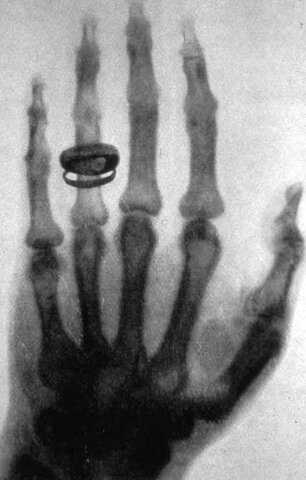

• Rayos x

Rayos x

El 8 de noviembre de 1895 el físico alemán Wilhelm Conrad Roentgen descubrió los rayos X mientras realizaba experimentos con tubos de vacío y un generador eléctrico.